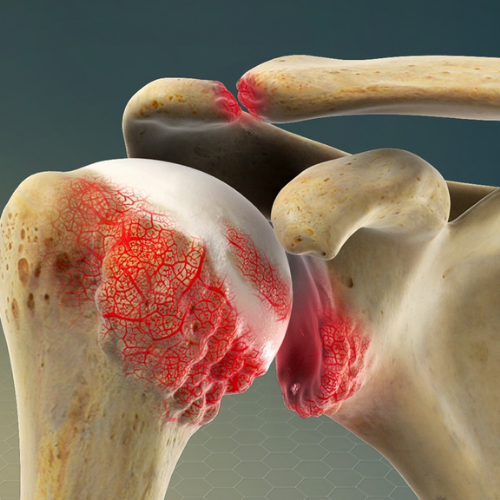

Shoulder pain can stem from many causes—rotator cuff injuries, frozen shoulder, tendonitis, bursitis, arthritis, or nerve impingement. While symptoms often feel similar, effective relief depends on accurately identifying the underlying condition. At REGENIQUE, we use advanced diagnostic tools and image-guided assessments to get to the root of your pain, ensuring that treatment is precise and recovery is long-lasting.

Conditions We Treat

Shoulder Joint Arthritis